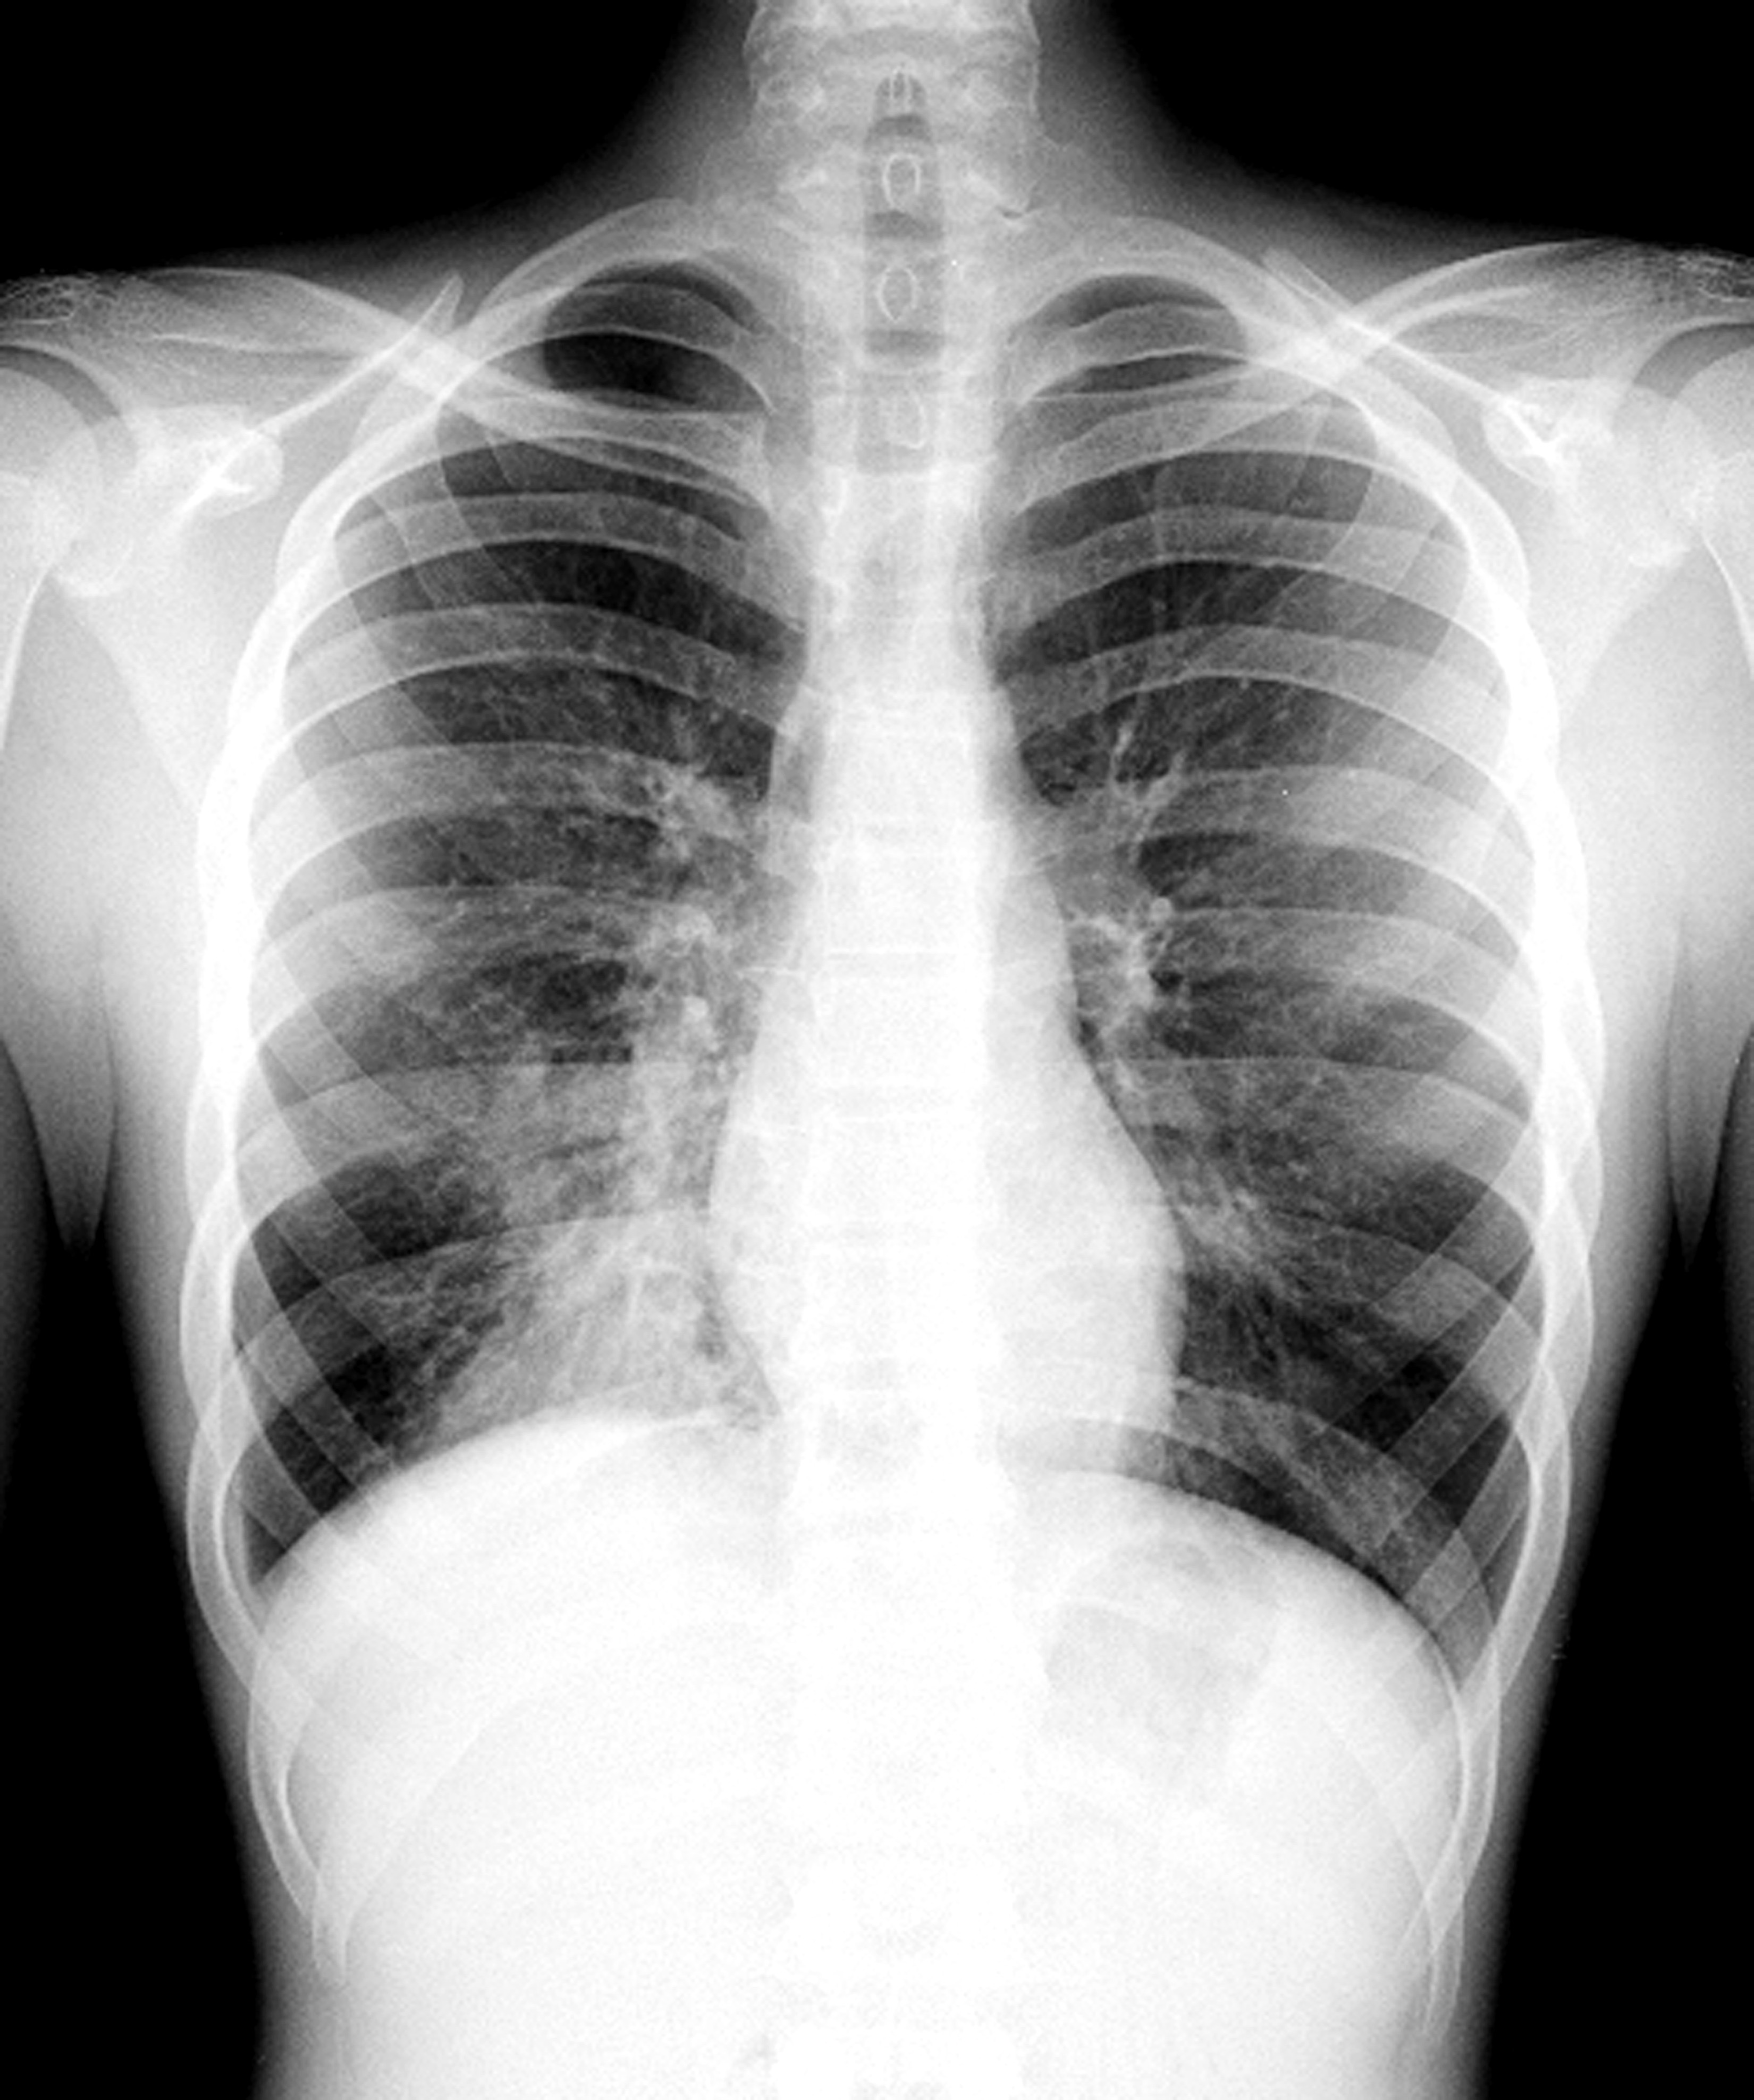

Пневмония - это серьезное заболевание легких, которое может быть вызвано различными причинами, включая бактериальные, вирусные и грибковые инфекции. Для того чтобы наглядно показать симптомы, диагностику и лечение этого заболевания, картинки могут быть очень полезны.

Картинки с симптомами пневмонии

В этом разделе представлены изображения, демонстрирующие различные симптомы пневмонии, такие как кашель, одышка, боль в груди и повышенная температура. Эти картинки могут быть использованы для обучения и презентаций в области медицины и здравоохранения.